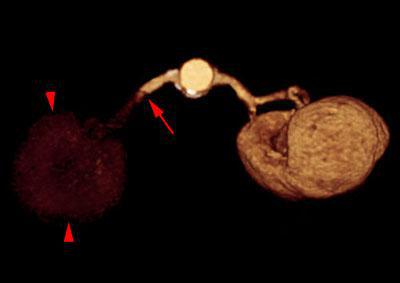

Infartos renales múltiples